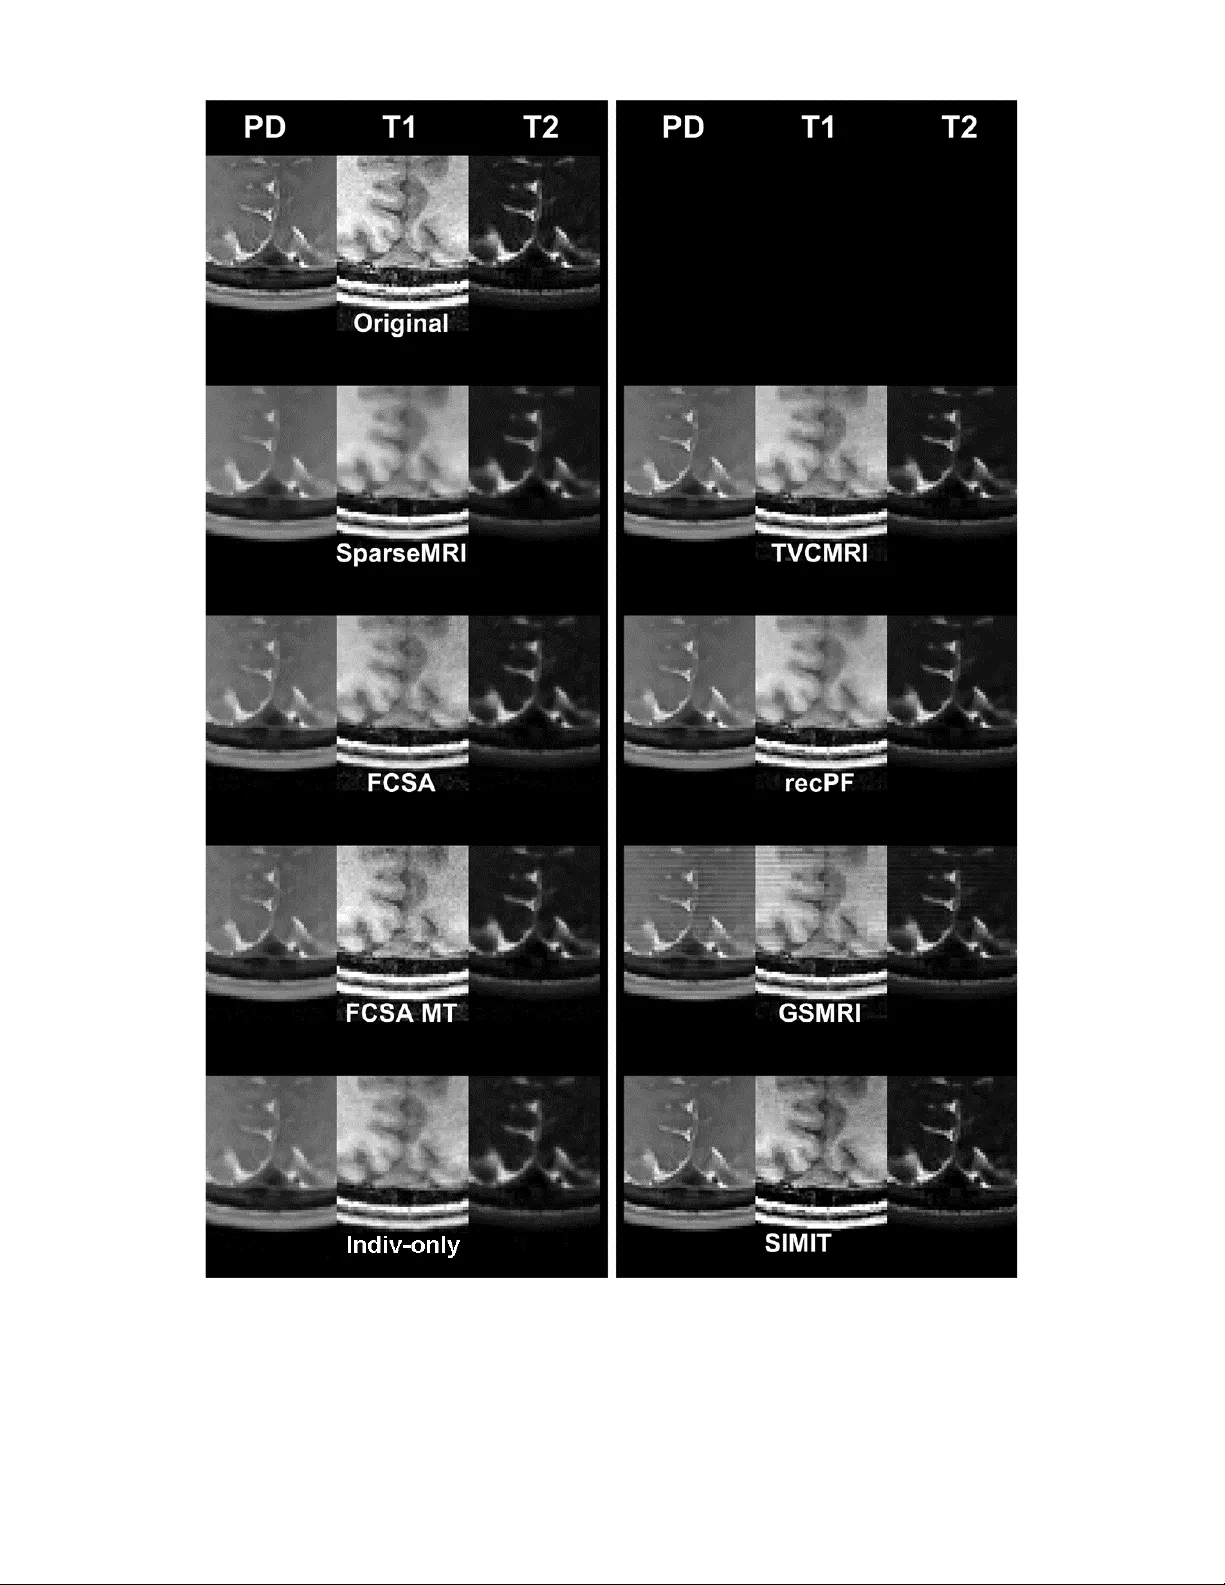

실험에서는 단일 채널 시뮬레이션 데이터와 실제 다채널 다대조 MRI(뇌, 무릎 등) 데이터를 사용해 세 가지 설정을 비교하였다. (1) 개별 정규화만, (2) 공동 정규화만, (3) 제안한 동시 정규화. 정량적 평가지표로는 PSNR, SSIM, 그리고 구조적 유사도 지표를 사용했으며, 정성적 평가는 2명의 신경방사선과 전문의가 블라인드 평가한 이미지 품질 점수를 활용했다. 결과는 제안 방법이 PSNR/SSIM에서 평균 2‑3 dB, 0.02‑0.04의 개선을 보였으며, 전문의 점수에서도 통계적으로 유의미한 상승을 기록했다. 특히 공동 정규화만 적용했을 때 관찰된 ‘특징 누출’ 현상이 거의 사라졌고, 이는 임상적 오진 위험을 크게 감소시킬 수 있음을 시사한다.